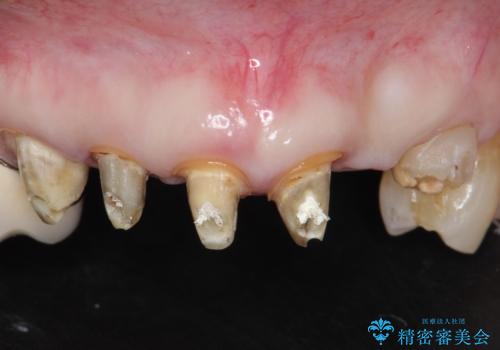

- 20年前に美容外科クリニックで治療した前歯をやりかえたいとのご希望で来院されました。

上の前歯6本はメタルボンドクラウン(内側が金属の被せ物)で補綴されており、顕著な歯肉退縮を認めました。

被せ物を除去したところ根管治療後の処置が不十分であったため、ファイバーコア(金属を用いない強くてしなやか材質の土台)を植立したのち、ジルコニアセラミッククラウンによる治療を行いました。